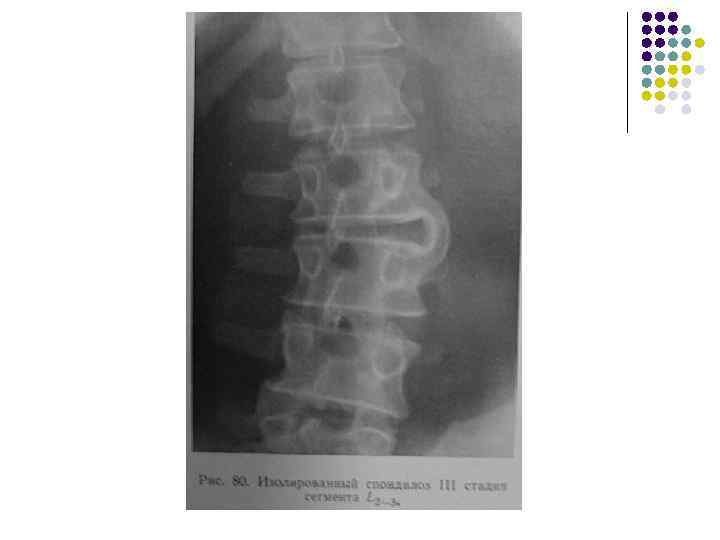

Спондилоз 1. 2. 3. Высота межпозвонкового диска не меняется. Обызвествления под передней продольной связкой начинаются над лимбусом и направлены вертикально. Нет субхондрального склероза поверхностей тел позвонков.

Стадии I стадия – обызвествление не выходит за уровень замыкающей пластинки позвонка II стадия – выход обызвествления за лимбус вплоть до тела смежного позвонка с образованием неоартрозов III стадия – слияние и фиксация позвонков подсвязочными обызвествлениями.